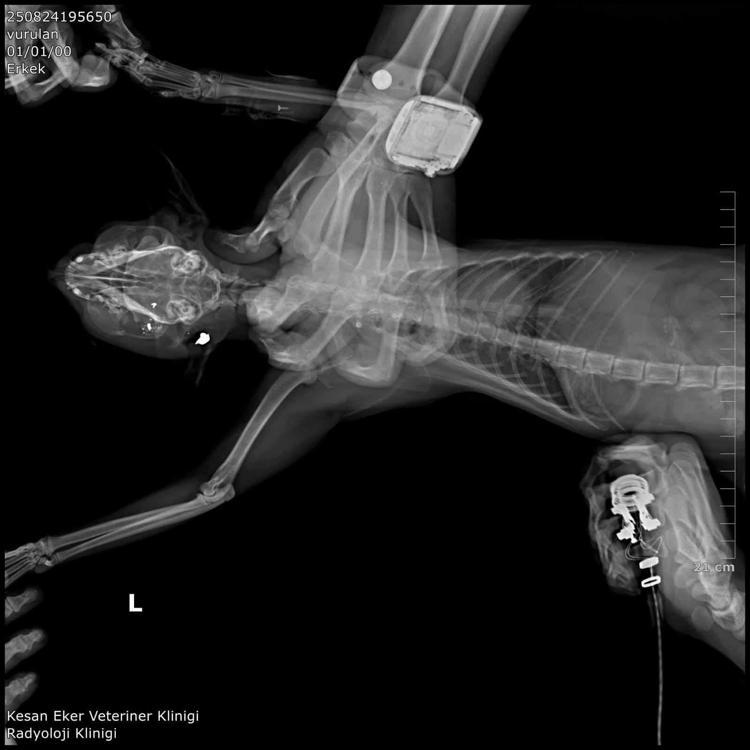

İpsala Cumhuriyet Başsavcılığı'nın olaya ilişkin hazırladığı iddianamede K.G., hakkında, 'Bir ev hayvanını veya evcil hayvanı kasten öldürme' suçundan 6 aydan 3 yıla kadar hapis cezası istendi. İddianamede, "Herhangi bir silah ateşleme görüntüsü tespit edilmese de şüphelinin ikamet ettiği evin bahçe kapısı önünde bir kedinin can çekiştiği ve bir kedinin de kaçtığının tespit edildiği, dosya kapsamında tanık olarak beyanı alınan S.Ç.'nin şüphelinin bahçe kapısı önünde bir kediyi yatar vaziyette gördüğünü, başını sevmek istediğinde kedinin ölü olduğunu fark ettiğini, kediyi eline aldığında başından kan aktığını görmesi üzerine yol üzerinde kalmaması amacıyla kediyi çöp tenekesinin içerisine bıraktığını, ölen ve yaralanan 2 kedi hakkında düzenlenen 25/08/2025 tarihli veteriner hekim ön muayene raporu ile çekilen radyografilerde ateşli silah yaralanması (kuş saçması) ile uyumlu patolojiler gözlemlendiği şeklinde rapor tanzim edildi.

Tüm dosya kapsamı incelenmekle şüpheli savunması, bilgi sahibi beyanları, İpsala İlçe Tarım Müdürlüğü'nün yazılı başvurusu, müşteki beyanı, kamera görüntüleri ve kriminal raporları birlikte değerlendirildiğinde, şüphelinin olay tarihinde müşteki Hüseyin Bülbül tarafından da beslenmekte olan sokak kedilerine ateş etmek suretiyle, bir kedinin ölümüne neden olarak üzerine atılı suçu işlediğine dair ve bir kedinin yaralanmasına neden olarak tariflenen suçu işlediğine dair hakkında kamu davası açmak üzere yeterli şüphe oluşturacak kadar delilin mevcut olduğu anlaşılmakla" denildi.